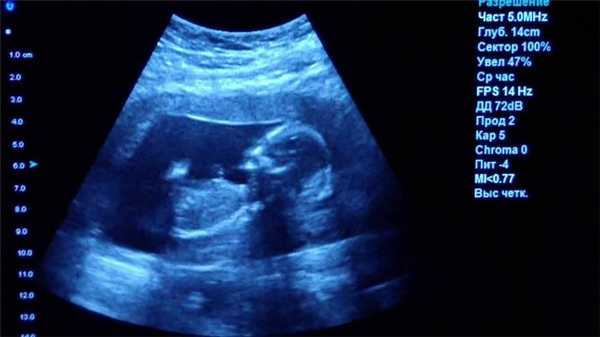

Лимфангиома у новорожденного. УЗИ. Крупная кистозная лимфангиома шеи справа (L )Типичная ультразвуковая морфология: мультикистозное образование с множеством перегородок и отсутствием сигнала потока при цветном допплеровском УЗИ.